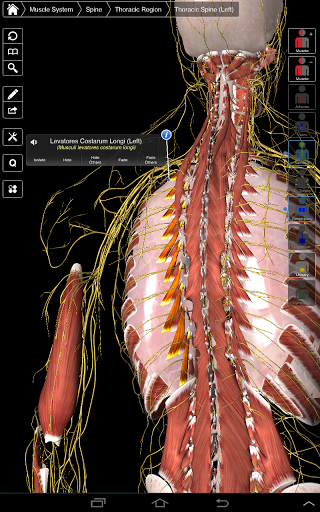

Essential Anatomy 3 reprezentuje najnowsze przełomowe technologie 3D i innowacyjny design. Najnowocześniejszy silnik graficzny 3D, zbudowany na zamówienie przez 3D4Medical od podstaw, zapewnia bardzo dokładny model anatomiczny i zapewnia doskonałą jakość grafiki, której żaden inny konkurent nie jest w stanie osiągnąć.

Aplikacja przedstawia unikalne podejście do uczenia się ogólnej anatomii. Grafika jest nieporównywalna i sprawia, że uczenie się, dzięki wykorzystaniu treści informacyjnej i innowacyjnych funkcji, jest bogatym i wciągającym doświadczeniem.

Ta aplikacja zawiera niezbędną anatomię dla 10 systemów:

⁃Muscles

⁃Nerwowość

Essential Anatomy 3 jest responsywny, wizualnie oszałamiający i pozbawiony wysiłku. Aplikacja jest w pełni 3D, co oznacza, że możesz zobaczyć dowolną strukturę anatomiczną w izolacji, a także pod dowolnym kątem.

Mądra funkcjonalność znajdująca się w aplikacji pozwala użytkownikowi usunąć warstwy mięśni za pomocą narzędzia "skalpela". Ta aplikacja zapewnia użytkownikom możliwość włączania / wyłączania systemów bez potrzeby wyłączania poszczególnych struktur lub pomieszania wielu predefiniowanych kart regionalnych, tak jak w przypadku innych aplikacji.

---- Ponad 4000 bardzo szczegółowych struktur anatomicznych

---- nomenklatura łacińska dla każdej struktury anatomicznej